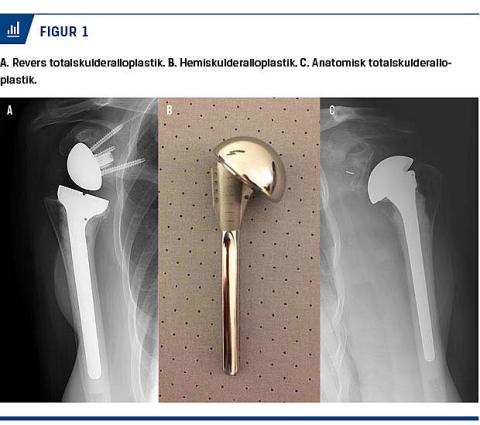

Udskiftning af kun ledhovedet med en metalprotese er mindre operationsteknisk krævende og eliminerer risikoen for eventuel løsning af ledskålsprotesekomponenten (Figur 1A). Halvproteser anvendes, hvor bruskdegeneration af ledskålen ikke skønnes at være betydelig, eller hos yngre personer, hvor risikoen for behov for en revisionsprotese på længere sigt skønnes at være betragtelig.

Ved denne type udskiftes såvel ledhovedet som ledskålen (Figur 1B). Totalskulderalloplastik (TSA) finder stigende anvendelse, da det er påvist, at TSA har bedre patientscore end hemiskulderalloplastik (HSA) [17, 18]. Af samme årsag anbefaler styregruppen for DSR, at TSA er førstevalg ved skulderartrose. Denne tendens er også understøttet af et større systematisk review over fire studier, hvor man har belyset forskellen mellem TSA og HSA, og det konkluderes, at TSA har størst effekt på smerte hos patienter med osteoartrose [18].

Ved rotator cuff-artropati, hvor de degenerative bruskforandringer er sekundære til rotator cuff-rupturer/-degeneration, og hvor protesekirurgi findes indiceret, anvendes helprotese af typen revers skulderalloplastik (Figur 1C). Her isættes en metalhalvsfære i ledskålen og en konkav komponent på ledhovedet, hvilket kan kompensere for den manglende stabilitet fra rotator cuff’en. Denne type protese isættes i stadig større grad, og således blev der i 2015 isat 354 omvendte TSA’er mod 211 i 2013 [3].